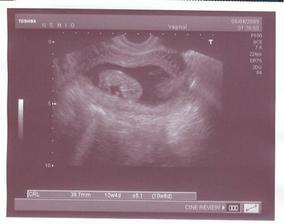

16.7. kontrola, bohužel tvrdnutí břicha, nasazeno magnesium 4x2 tablety, hlavně se šetřit. Pan doktor nám přeměřil Honzika a vážil 820gramů, bohužel délku nám neprozdadil. 13.8. nás čeká další kontorla.